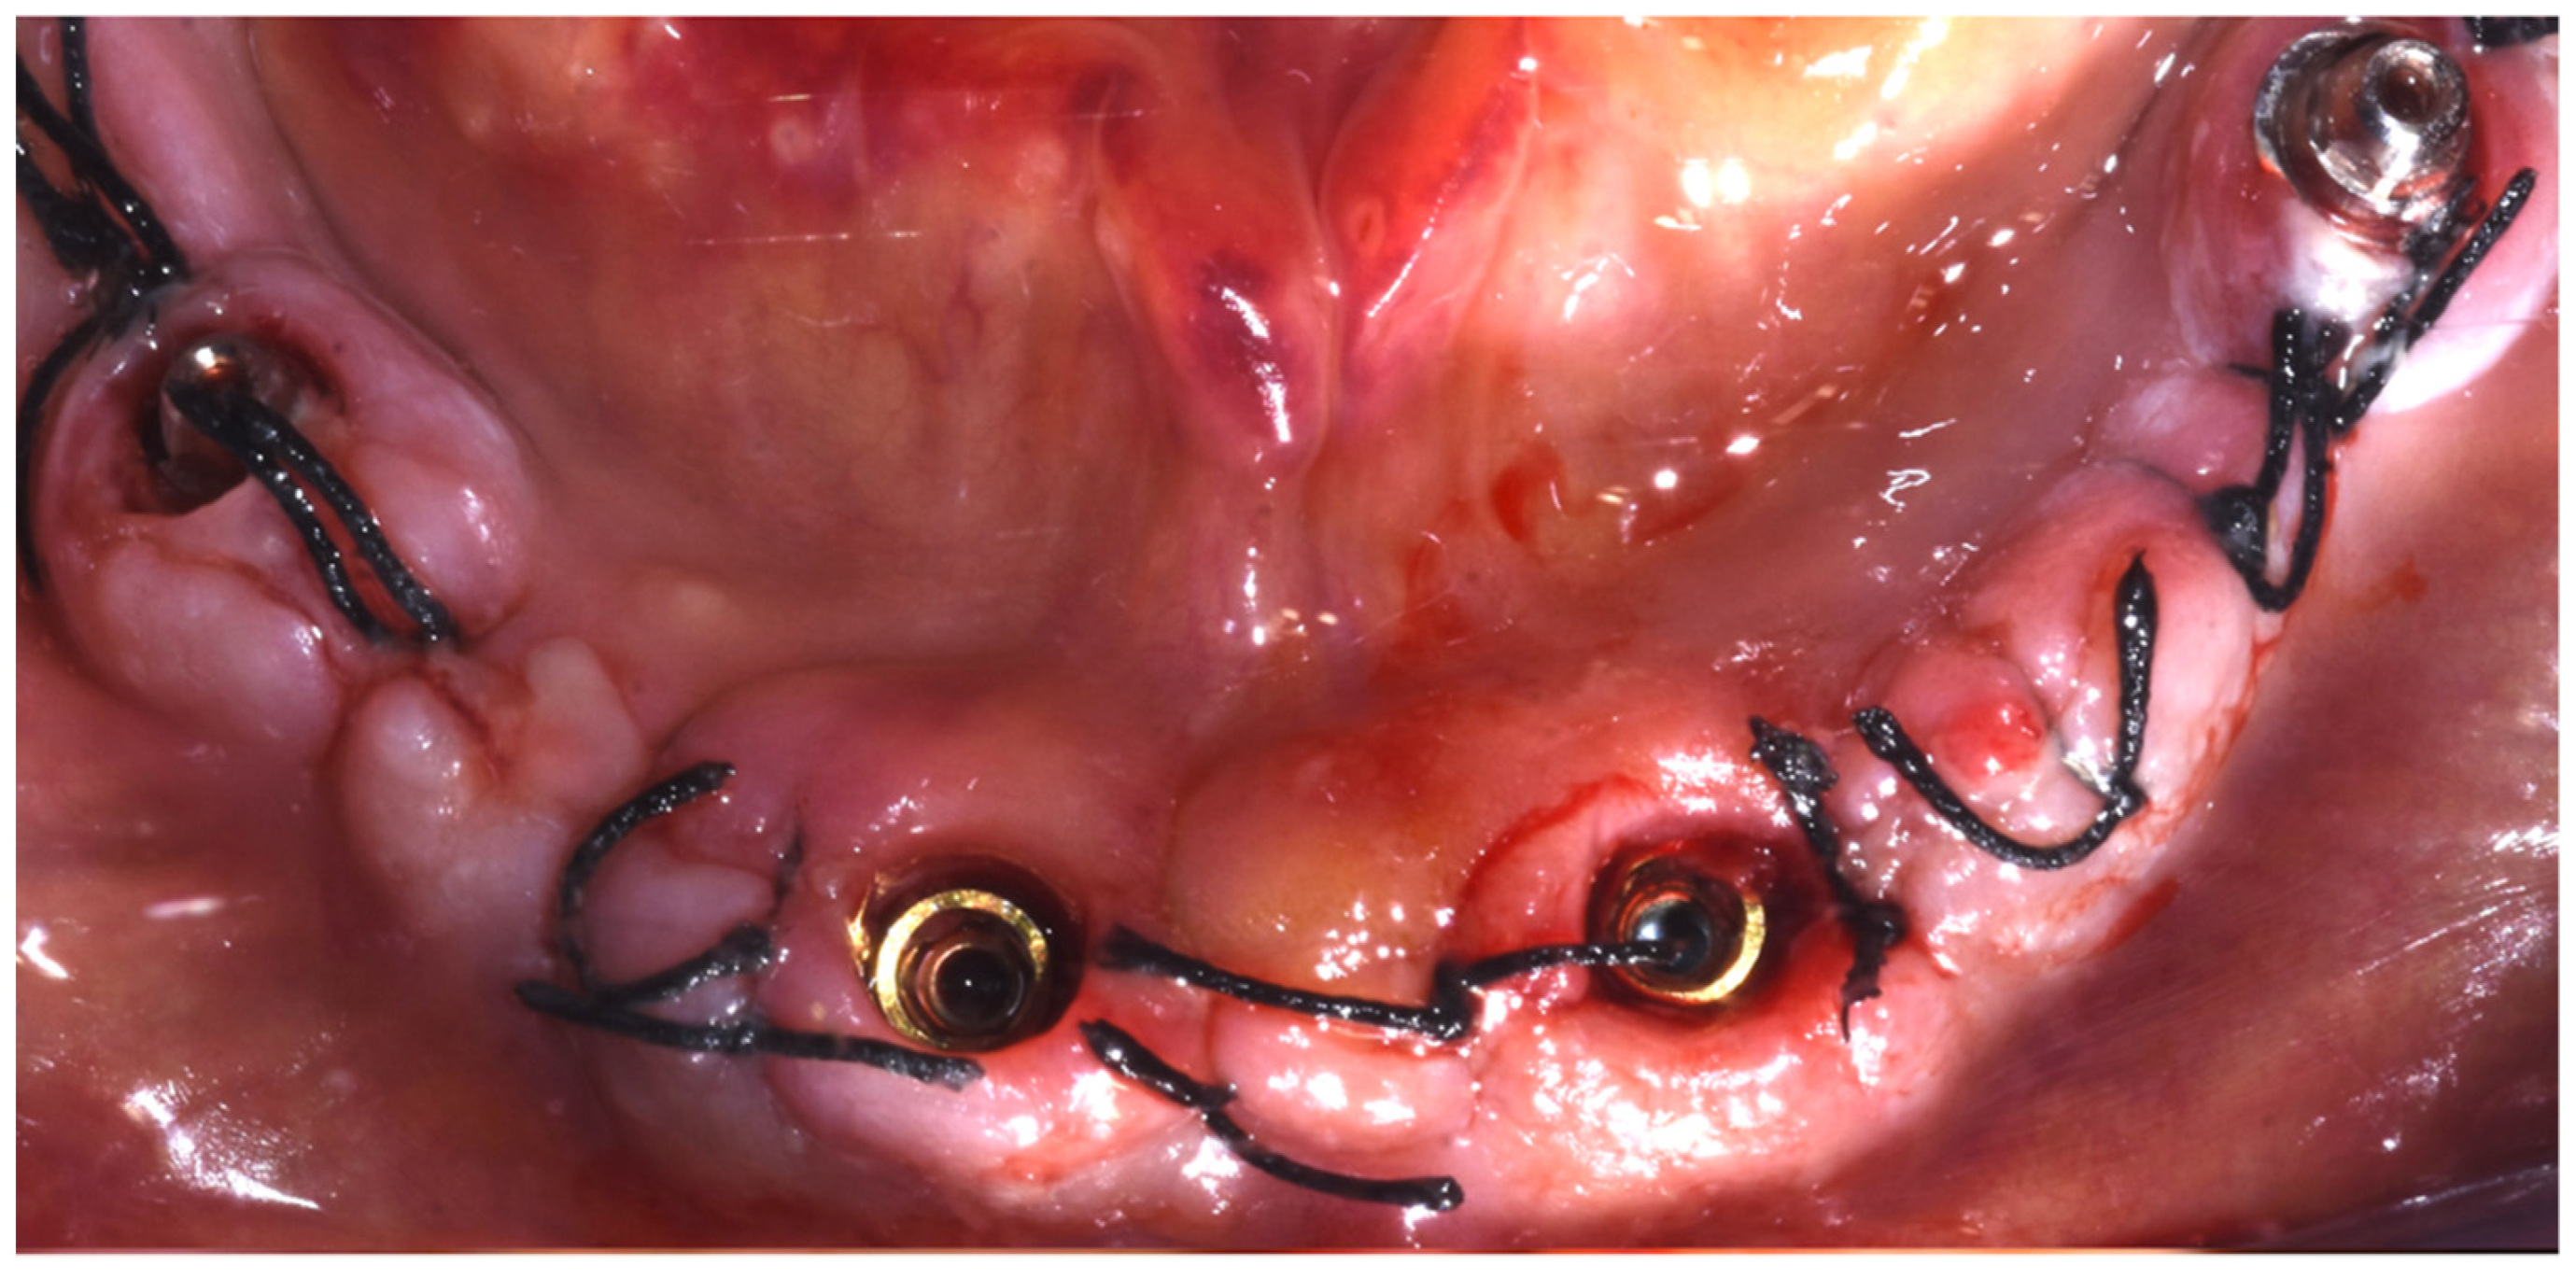

2. Case Report

Surgery Appointment